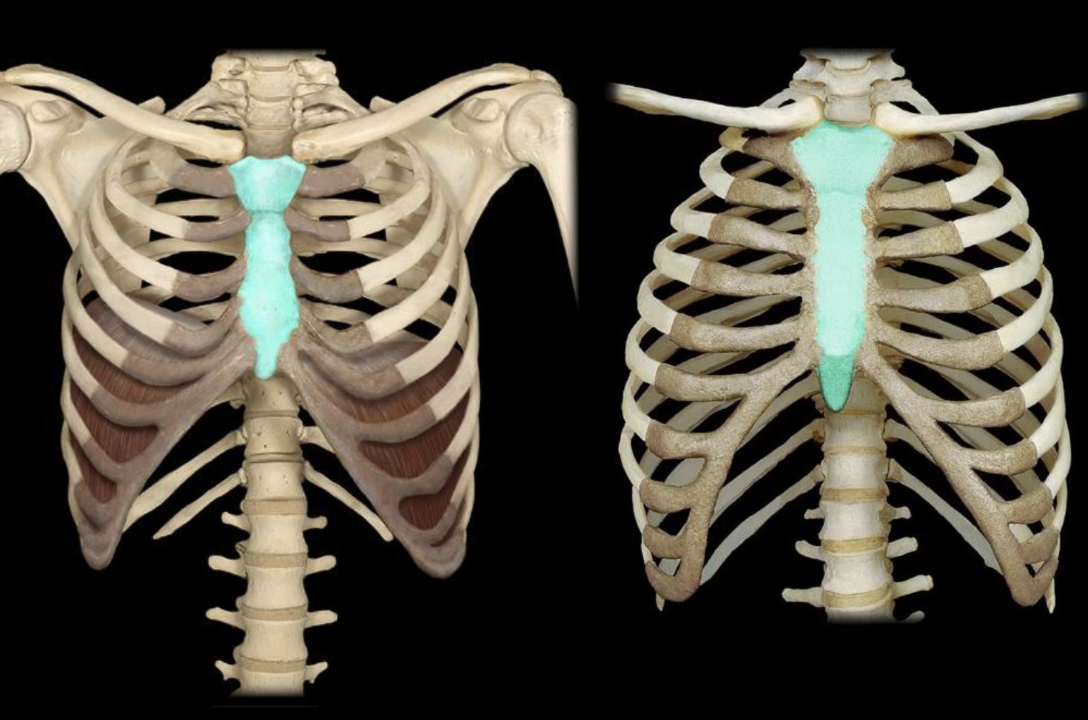

12

New cards

styloid process

knowt flashcard image

13

mastoid process

14

thoracic cage

sternum

manubrium

xiphoid process

ribs

true ribs

false ribs

floating ribs